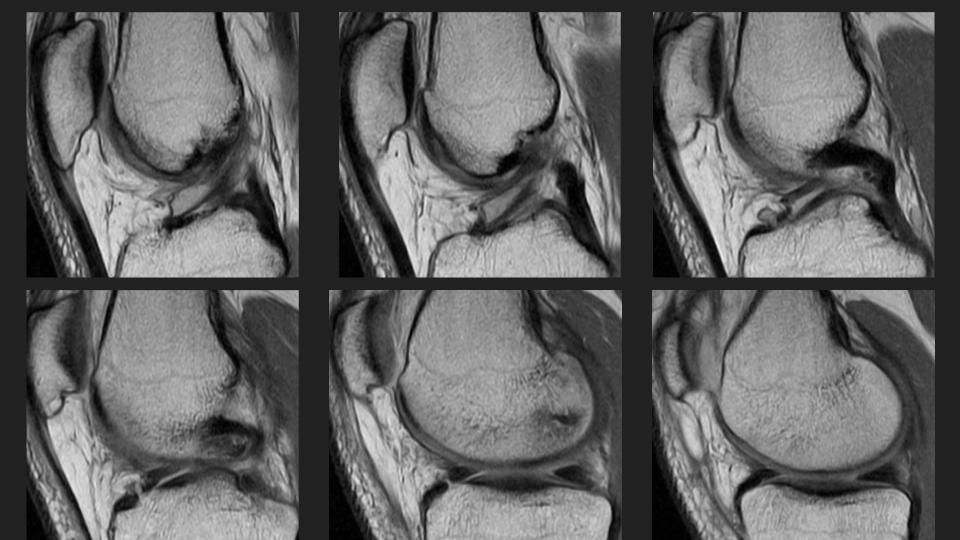

27M knee pain

This is an anteromedial meniscofemoral ligament. It looks alot like the relatively common ligamentum mucosum, but is is rare (approx 0.4% incidence) and inserts onto the central aspect of the anterior horn medial meniscus rather than the patella. It is eye-catching, but incidental and should not be resected. Reference article.

meniscofemoral ligament ( RID2806 )